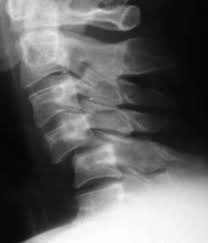

52세 여성이 집에서 계단을 내려오다가 발을 헛디뎌 2.5m 높이에서 추락하여 응급실로 이송되었다. 환자는 의식이 명료하나 하지의 감각과 운동 능력이 저하되어 있었다. 활력징후는 혈압 90/60 mmHg, 맥박 45 회/분, 호흡수 18회/분, 체온 36.5도이다. 환자의 손과 발은 따뜻했으며 직장수지검사에서 항문 괄약근의 긴장이 감소되어 있었다. 경추 X선 사진이다. 저혈압의 원인은?

• 추락으로 인한 외상으로 spinal cord injury가 발생하여 감각저하, 운동능력 저하 및 저혈압, 서맥, 항문괄약근 긴장 감소가 발생했다.

• 다음의 소견들은 신경인성 쇼크를 시사하는 소견들이다.

(1) 혈관 확장: 신경인성 쇼크는 척수 손상으로 인해 교감신경계의 기능이 저하되면서 혈관이 확장된다. 일반적으로 교감신경은 혈관을 수축시켜 혈압을 유지하지만, 척수 손상으로 이 기능이 상실되면 혈관이 확장되어 말초로의 혈류가 증가하게 된다. 이로 인해 손과 발 등의 말초 부위로 혈류가 증가하며 피부가 따듯해지는데, 다른 유형의 쇼크는 보통 말초혈관이 수축하는 것과 대조적이다.

(2) 저혈압: 혈관이 확장되면서 말초 저항이 감소하고, 결과적으로 혈압이 떨어진다.

(3) 서맥: 교감신경계의 억제로 인해 심박수가 감소할 수 있다.

(4) 항문 괄약근 긴장 감소: 신경학적 손상으로 인해 항문 괄약근의 긴장이 감소될 수 있다.